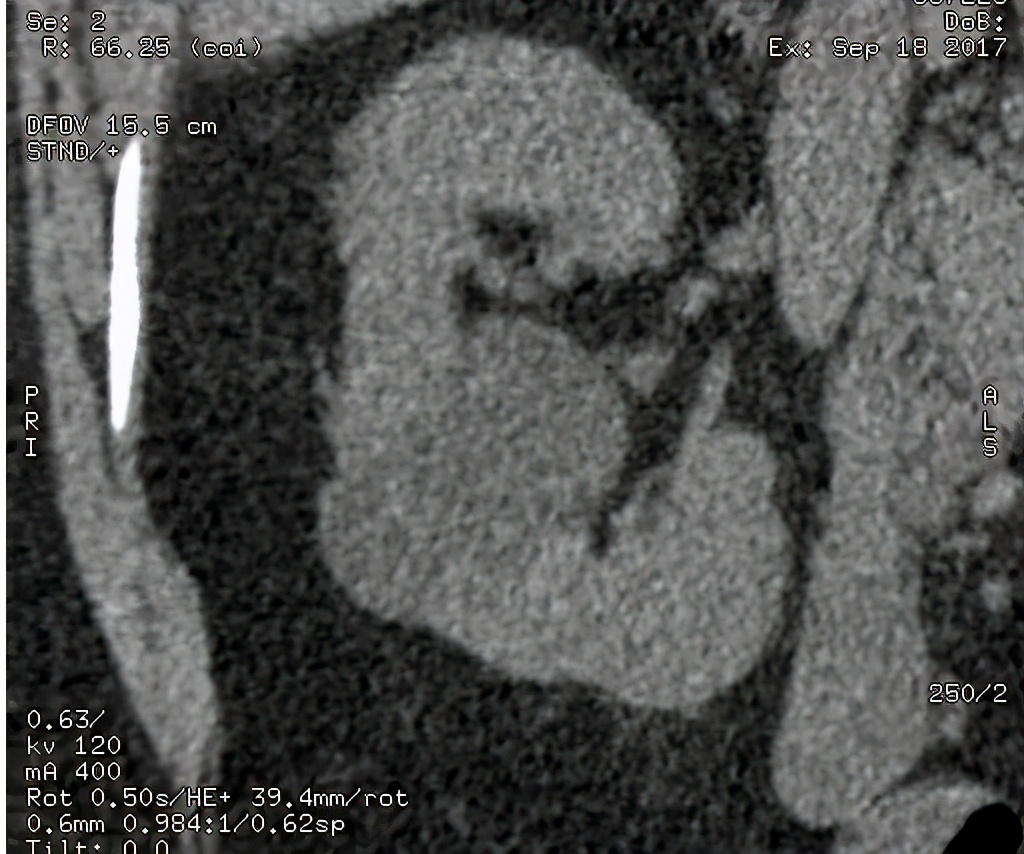

上图所示:38岁女患,有发热、脓尿等症状,临床诊断为泌尿系感染,行尿路造影检查,可见(左侧)输尿管下段管壁增粗,均匀强化,考虑输尿管炎症可能。